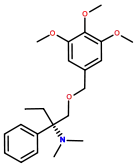

Phenalkoxams

- Dextropropoxyphene (propoxyphene)

- Dimenoxadol

- Dioxaphetyl butyrate

- Levopropoxyphene

- Norpropoxyphene

- Pyrroliphene

Structures

| Phenalkoxams | ||||

|---|---|---|---|---|

Dextropropoxyphene |

|

|

|

|